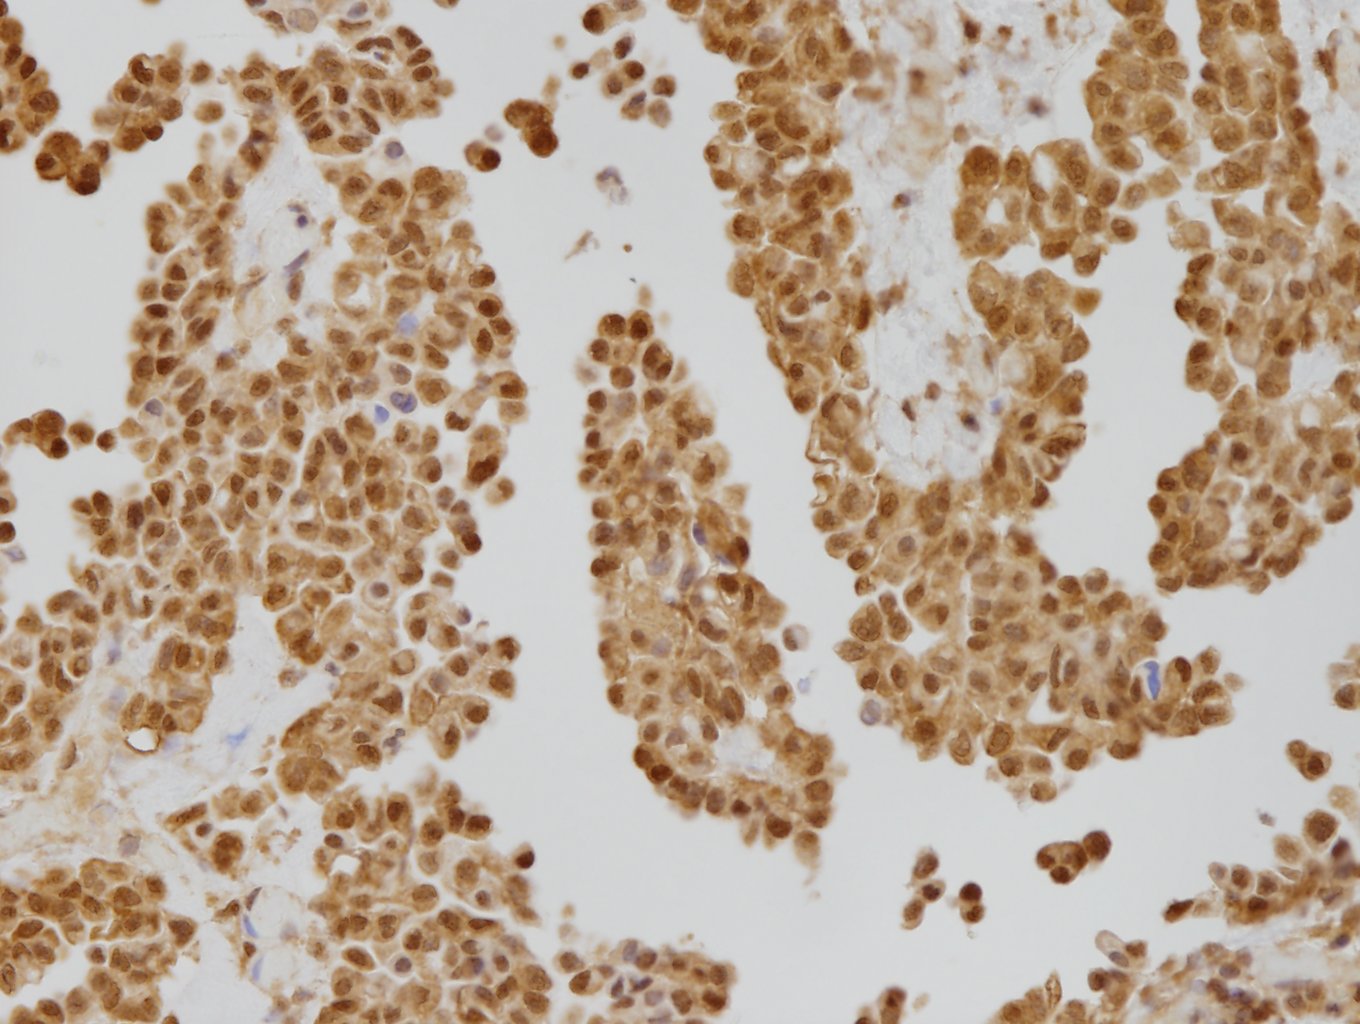

特異性および抗原分布

ヒトMTAP(methylthioadenosine phosphorylase)タンパク質と特異的に反応する。MTAPは、ポリアミン合成に伴って生じるMTA(5'-methylthioadenosine)を分解し、アデニンおよびメチオニンのサルベージ経路に関与する酵素である(1)~(4)。MTAP遺伝子はヒト9番染色体の短腕(9p21.3)に位置し、同領域にあるCDKN2A遺伝子と近接している(1)~(4)。両遺伝子は中皮腫などで共欠失するため、MTAPの免疫組織化学染色(IHC)は、Fluorescence in situ ハイブリダイゼーション(FISH)法によるCDKN2Aのホモ接合性欠失検出(CDKN2A FISH)の代替アッセイとして認識されている(2)(5)~(7)。正常では、中皮細胞、平滑筋細胞、尿路上皮細胞など、ほとんどの細胞の細胞質に反応がみられる(3)(6)。腫瘍では、中皮腫(胸膜: 約50%、腹膜: 約5~10%)、膵管腺癌、尿路上皮癌、非小細胞肺癌などで、MTAPの細胞質からの消失(MTAP loss)がみられることがある(1)(4)~(7)。胸膜中皮腫の組織型別では、上皮様中皮腫35%(8)~67%(2)、二相性中皮腫59%(8)、肉腫様中皮腫61%(9)~83%(8)でMTAP lossが報告されている。胸膜中皮腫と反応性中皮過形成の判別において、BAP1 IHC(核からの消失)、MTAP IHC(細胞質からの消失)、CDKN2A FISH(ホモ接合性欠失)による遺伝子異常に基づいた補助的アッセイが有用であると報告されている(2)(3)(5)(10)。

注1: MTAPが発現している細胞では、細胞質の他に核にも染色がみられる場合がある。

注2: MTAP lossを示す細胞では、細胞質の染まりは消失しているが核に染色がみられる場合がある。

注3: MTAP lossの有無を評価する際は、内在性陽性コントロール(内皮細胞、炎症性細胞、線維芽細胞など)が陽性であることを必ずご確認のうえ判別ください(5)(10)。